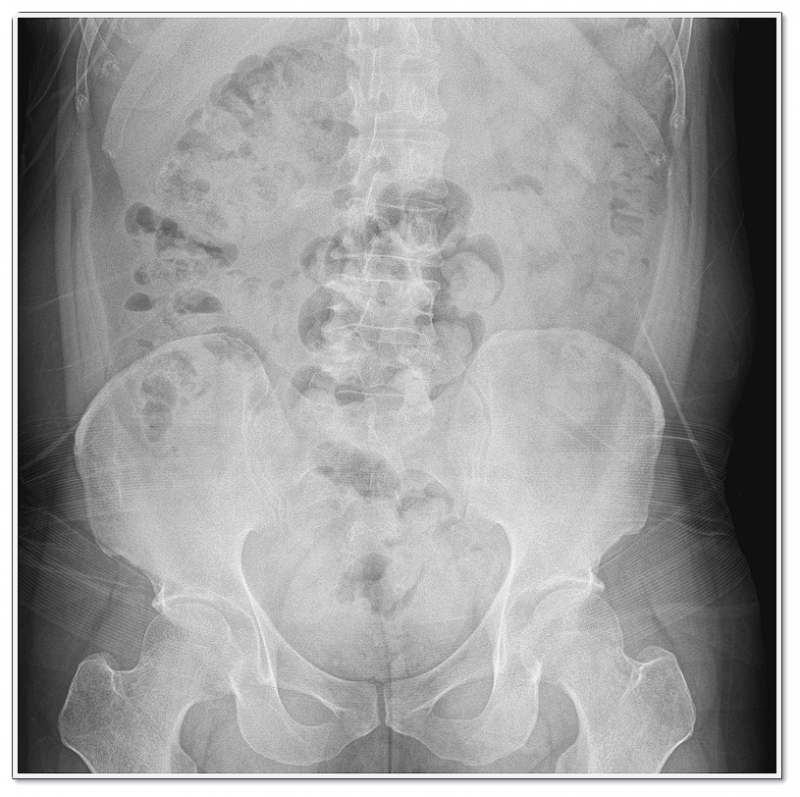

어떤 경우에는 근육의 과도한 긴장이나 척추 정렬의 미세한 불균형이 주된 원인이 되기도 하죠.

그래서 단순히 디스크만 보는 것이 아니라, 근육 상태와 척추 주변 조직의 긴장도도 함께 살펴보는 게 중요합니다.